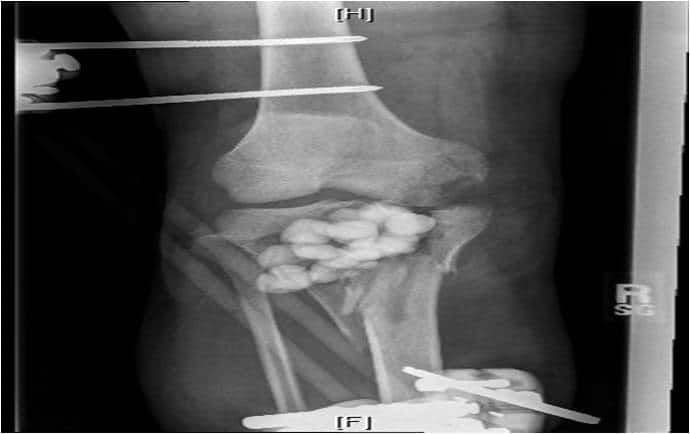

1. див. зобр. 7. Передньозадня рентгенограма внутрішньосуглобового перелому коліна.

Зобр. 7